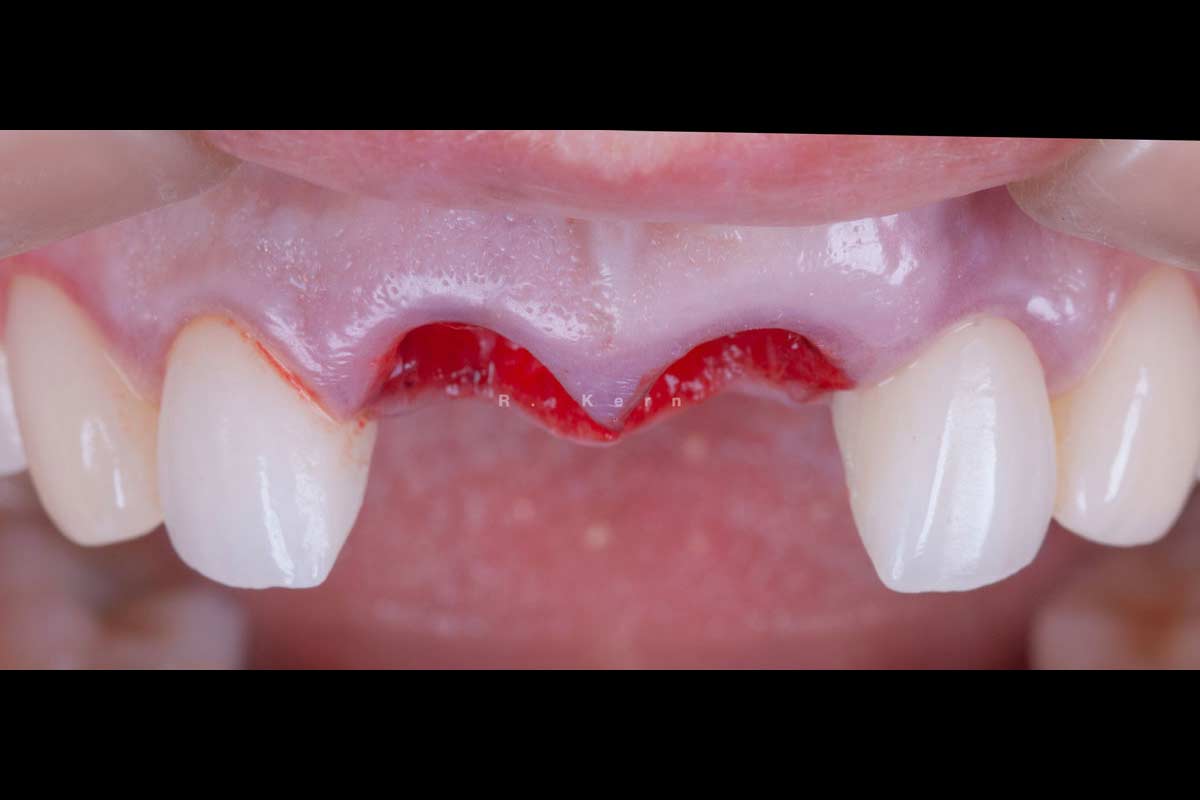

05/12 - Soft tissue situation. Buccal soft tissue augmentation planned at 21

Immediate implant placement and periimplant bone augmentation using cerabone® - Dr. R. Kern